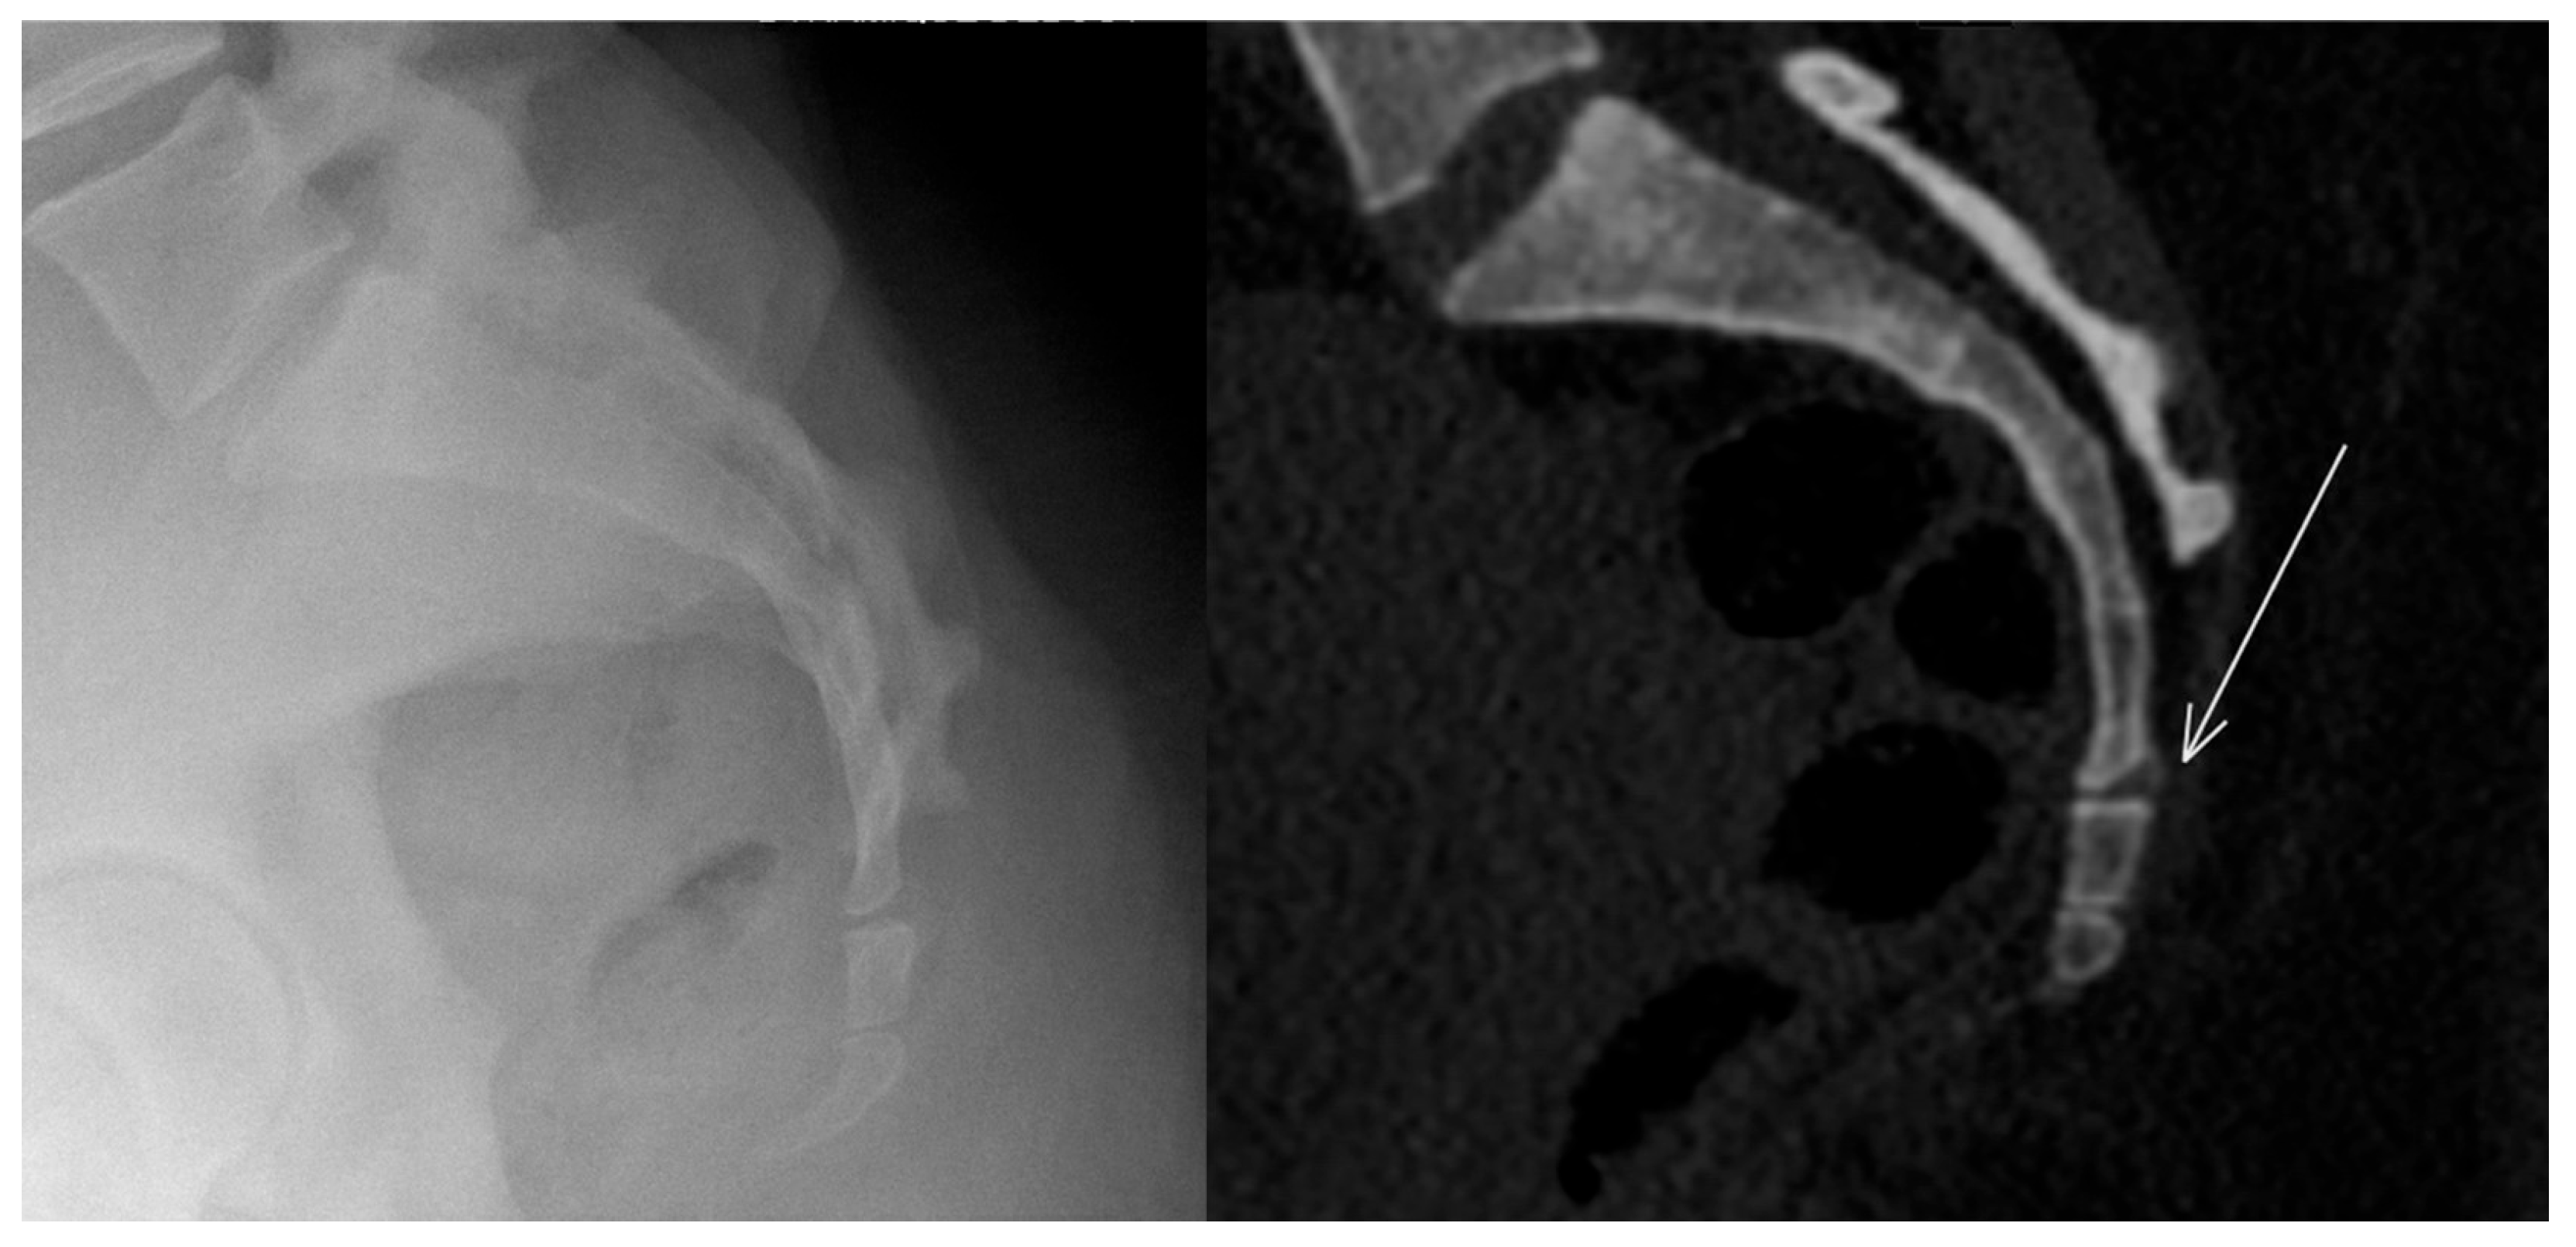

3.2. Lower Limb Involvement

- Park, S.M.; Baek, J.H.; Ko, Y.B.; Lee, H.J.; Park, K.J.; Ha, Y.C. Management of acute calcific tendinitis around the hip joint. Am. J. Sports Med. 2014, 42, 2659–2665. [Google Scholar] [CrossRef]